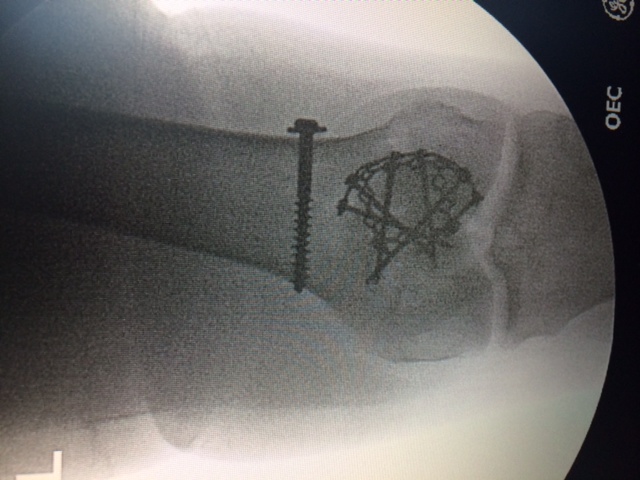

On May 25, 2010, I survived a head-on collision on Route-87. An 89-year-old man with dementia crossed over the meridian and hit me head on. After paramedics took 1 1/2 hours to free me from the vehicle, I was air lifted to a facility in Westchester, who wanted to amputate my lower right leg. At this facility, I had 2 surgeries there to "clean out" the right tibia and leg. My ankle was crushed from the accident. When I was there, I called my friend to help me. My friend, who used to be a PA at HSS, recommended me to Dr. Helfet, who eventually saved my leg after 3 surgeries. I consider him to be the Guru of orthopedic surgeons. Six months after the surgeries, I was back in high heels. Soon after that, I could hike mountains. If it was not for Dr. Helfet and HSS, I would not be where I am today.